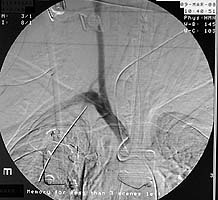

Enclosed are three figures--the CXR of a male with a left to right transmediastinal GSW of upper chest--no hard signs of vascular injury except for about 1000 cc blood out of left chest tube which eventually stopped without surgery. Next is angio #1 showing intimal defect in innominate artery right at the takeoff of the Rt subclavian and carotids. F/U angio one week later--no surgery--documents complete resolution of the intimal injury. There were no symptoms, including the blood from the left chest, attributable to this injury, thus fulfilling the criteria for observation.

Initial CXR